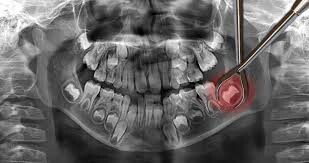

Impacted wisdom teeth hardly ever erupt

Not all wisdom teeth make it out of the gums. Some get impacted, meaning they are trapped in the jawbone or blocked by other teeth. This often happens when the wisdom teeth come in at an awkward angle. Impacted wisdom teeth can cause severe pain and will need to be removed through a surgical procedure.